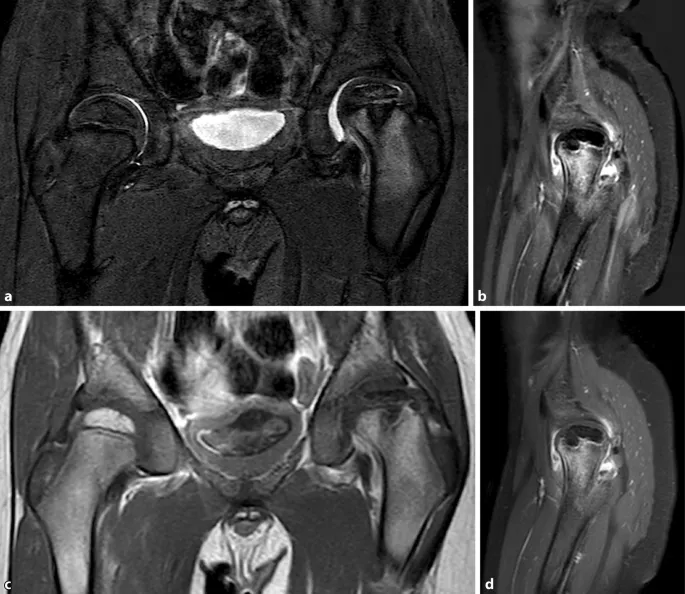

Magnetresonanztomographie (MRT): Die MRT bietet die Möglichkeit, Durchblutungsstörungen im Hüftkopf schon sehr früh zu erkennen, oft bevor sie auf dem Röntgenbild sichtbar werden. Sie kann Knochenmarködeme und das genaue Ausmaß der Nekrose (des abgestorbenen Gewebes) im Hüftkopf darstellen. Dies ist besonders wertvoll, um den Schweregrad der Erkrankung präzise einzuschätzen und die Therapieplanung zu optimieren.

Röntgen: Die Röntgenaufnahme des Beckens in zwei Ebenen (anteroposterior und Lauenstein-Aufnahme) ist der Goldstandard zur Bestätigung der Diagnose von Morbus Perthes. Sie ermöglicht es dem Arzt, den Zustand des Hüftkopfes detailliert zu beurteilen. In frühen Stadien können die Veränderungen auf dem Röntgenbild subtil sein, wie eine leichte Verdichtung des Hüftkopfes oder eine Verbreiterung des Gelenkspalts. Im weiteren Verlauf der Erkrankung werden typischerweise eine Abflachung und Fragmentierung des Hüftkopfes sichtbar.